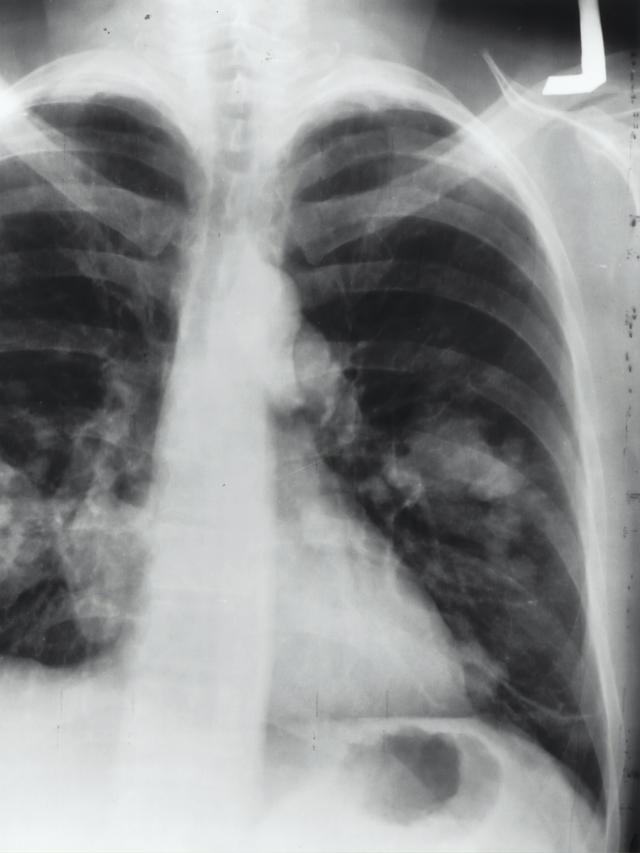

Tujuan utama peringatan ini tentunya untuk meningkatkan kesadaran masyarakat tentang pentingnya menjaga kesehatan paru-paru serta risiko penyakit paru-paru seperti asma, tuberkulosis, dan penyakit paru obstruktif kronis (PPOK).